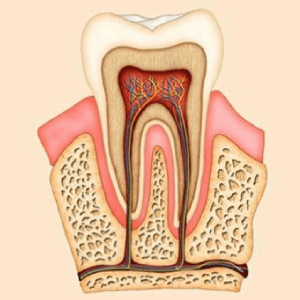

Step-by-Step Root Canal Procedure

We follow a modern and scientific approach to ensure success and patient comfort:

• Tissue & Nerve Removal

Infected pulp and nerves are removed using advanced rotary instruments.